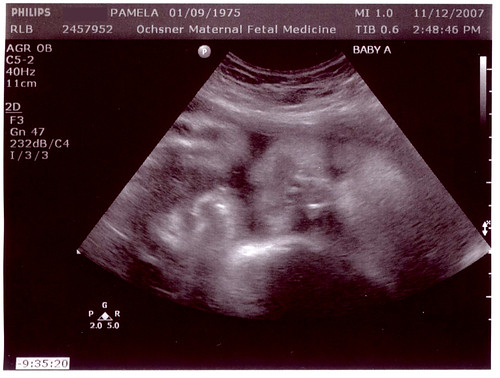

Oh, pics? Want to see them? C was being uncooperative, so we only have A & B. But like it matters – they basically look all the same anyway. 😛